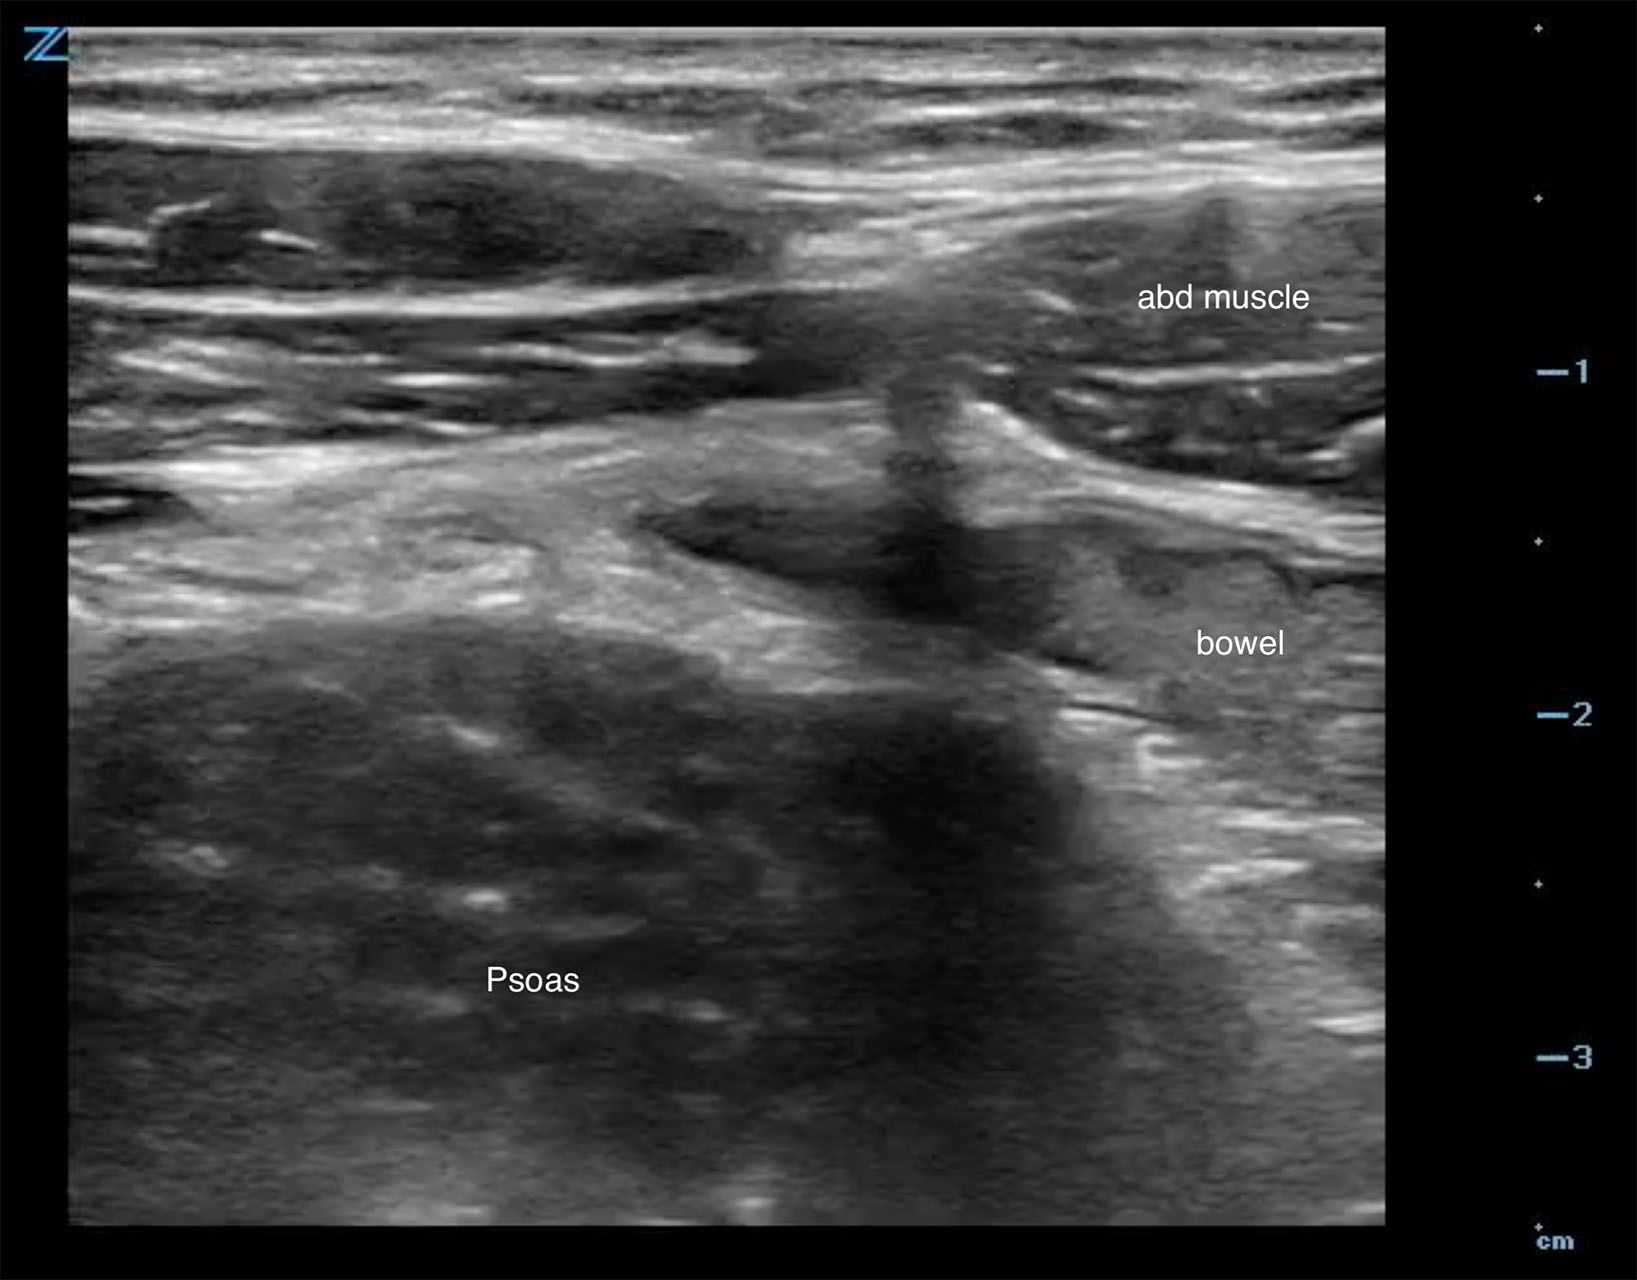

- Start in the RLQ with slow, steady pressure (graded compression) and find the psoas muscle. (Fig. 3)

- Figure 3. The psoas muscle is seen here posterior to the anterior abdominal musculature in the RLQ